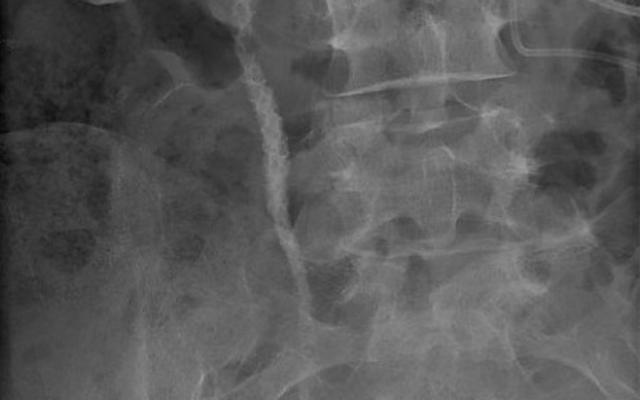

Diagnose in beeld

Hier vind je alles op het gebied van ‘Urologie’. Ben jij een uroloog? Volg dit vakgebied en ontvang een mail wanneer er een nieuw artikel of een nieuwe toets of beeldquiz binnen jouw specialisme is gepubliceerd. Zo ben je altijd op de hoogte.